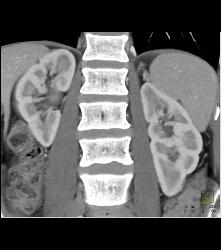

Scarring Left Kidney